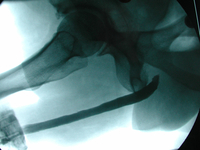

Harnröhrenverengungen (sog. Hanrröhrenstrikturen oder Harnröhrenstenosen) haben oft vermeintlich kleine Ursachen. So kann beispielsweise eine „harmlose” Entzündung der Harnröhre oder aber auch das „einfache” Einlegen eines Blasenkatheters zu einer Vernarbung mit Harnröhrenverengung führen. Neben den endoskopischen Verfahren, bei denen per kaltem Schnitt oder per Laserschnitt (z.B. mit dem Holmium-Laser) die Verengung beseitigt wird, bestehen in der urologischen Klinik im linikum Ingolstadt umfangreiche Erfahrungen mit der offenen Rekonstruktion von wiederkehrenden Harnröhrenverengungen und auch komplett zerstörter Harnröhren nach Unfällen. Die Harnröhrenchirurgie stellt wegen unterschiedlichster anatomischer Gegebenheiten und auch dem äußerst verschiedenen Ausmaß der Harnröhrenerkrankungen besonders hohe Anforderungen an den Operateur. Die Rekonstruktion der Harnröhre bei Verengungen erfolgt durch gestielte oder freie Transplantate, wobei der Harnröhrenrekonstruktion mittels freier Wangenschleimhauttransplantaten ein besonders hoher Stellenwert zukommt. Je nach individuellen Gegebenheiten können ein- oder mehrzeitige Operationsverfahren notwendig werden.